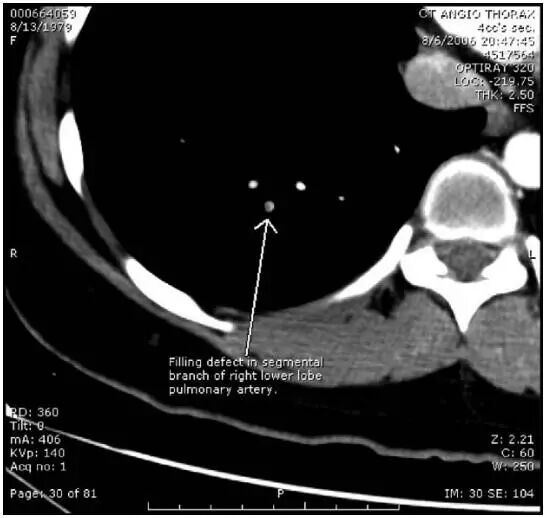

急查心电图提示窦速,其余未见明显异常。胸片未见明显异常。D-dimer回报495.1ng/ml(ELISA法)。考虑患者典型呼吸性胸痛及不能用其他原因解释的窦性心动过速,行肺栓塞CT扫描,提示右肺下叶动脉分支充盈缺损(图1),确诊为右肺下叶亚段肺栓塞。

图1 肺栓塞CT提示右肺下叶动脉分支充盈缺损,箭头所示,明确肺栓塞诊断